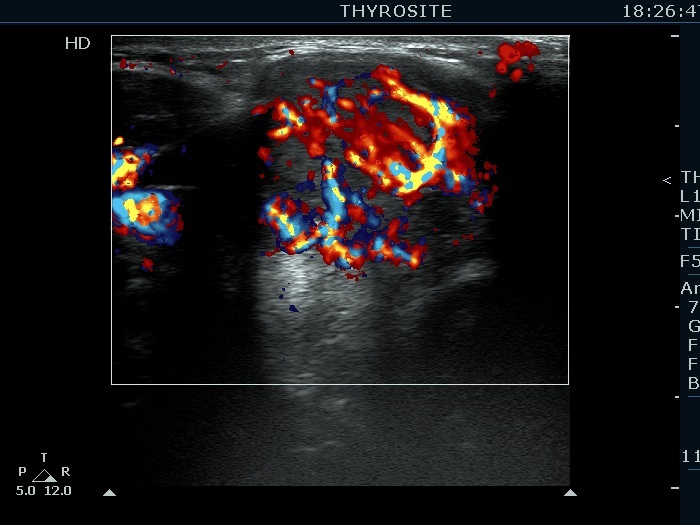

Extrathyroidal spread - case 2113 (ultrasonographic picture 8)

Right lobe, longitudinal scan

Isthmic part of the right lobe, transverse scan, color Doppler mode. A chaotic-type vascular pattern is demonstrated.